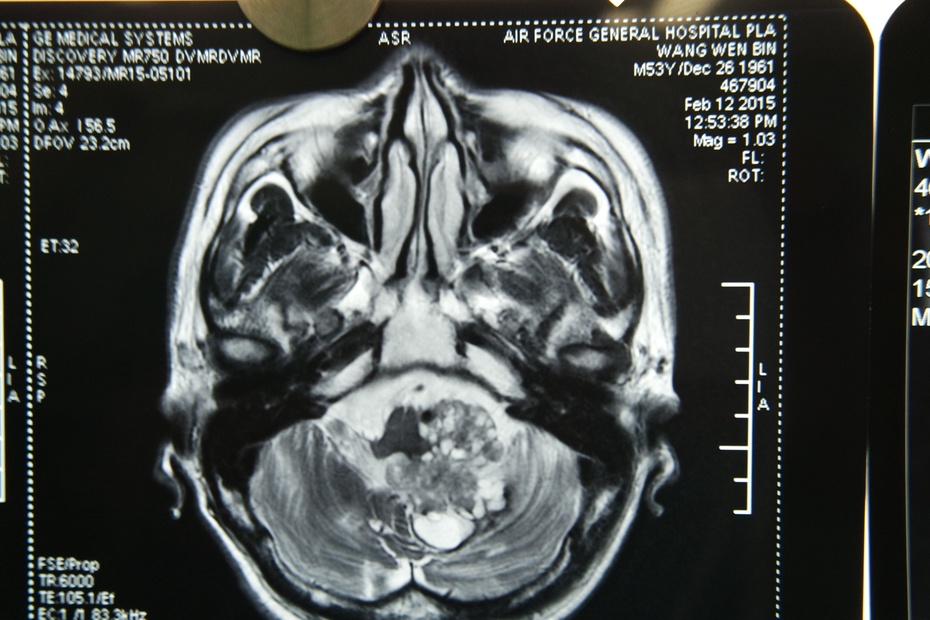

影像学检查,明确诊断四脑室肿瘤,脑干受压,不同程度的脑积水,

第四脑室分顶、底和外侧界三部分,为延髓、桥脑和小脑间的间隙,向上借中脑导水管与第三脑室相通,向下与延髓中央管相接,两侧为侧隐窝,经外侧孔与桥脑小脑角相通,四脑室底为菱形窝,被正中沟分为左右两半,中间横行的为髓文,旁边为界沟,界沟与正中沟之间为内侧隆起,菱形窝下角、其下界为闩,四脑室底部分布有较多脑神经功能核团。四脑室肿瘤包括原发于第四脑室本身组织的肿瘤如室管膜瘤、脉络丛乳头状瘤,还有来源于第四脑室周围的组织,其生长进入四脑室的肿瘤如髓母细胞瘤、血管母细胞瘤和星形细胞瘤等。不同的四脑室肿瘤其核磁共振检查( MRI) 表现不同,室管膜瘤呈团块状低、中等T1 信号及不均质高T2信号,增强后见病灶明显强化,常伴有脑积水; 脉络丛乳头状瘤的T1 为低信号、T2 为高信号,增强检查肿瘤显著对比增强; 四脑室纤维状细胞星形细胞瘤、室管膜瘤与脉络丛乳头状瘤在核磁共振鉴别较难; 血管母细胞瘤60%为囊性伴有壁结节,40%为实性,囊性者T1 为低信号,T2 呈明显高信号,增强扫描壁结节强化,肿瘤内有时可见血管流空现象,诊断一般不困难。髓母细胞瘤多起源于四脑室顶部,大多发生在10 岁以下的儿童,肿瘤病程短,恶性程度高,持续性的头痛、呕吐、小脑共济失调等症状很早即可出现,MRI 在T1 显示长信号,T2显示长信号,并且T2 信号较室管膜瘤更强,四脑室往往被推向前方或消失,有典型的水肿带位于肿瘤周围,钙化及囊变不多见。由于肿瘤不同的病理类型、发生的部位及生长方向不同,手术中的处理也不尽相同。利用核磁共振检查,分析出肿瘤的生长部位、范围、大概质地、血运等情况,给术者在术中不同入路切除肿瘤提供重要信息,在最大程度地保存功能情况下全切除肿瘤。全身麻醉后取俯卧位或侧俯卧位,俯卧位有利于明确术中定位,但需注意脑部静脉回流情况及气管插管接麻醉机后的气道阻力等情况,避免开颅后脑膨出等情况。侧俯卧位,利于避免静脉回流障碍,清楚显露术野。神经外科专用手术床的多角度移动有利于清楚的显露术野。由于小脑蚓部构成第四脑室顶,经小脑下蚓部入路,可满意地暴露四脑室上部肿瘤,但对外侧隐窝肿瘤显露相对不利,术后也易发生小脑缄默征等并发症; 小脑延髓脉络膜裂位于延髓背侧与小脑蚓部、扁桃体及小脑半球下缘之间的一个自然间隙,连接延髓背侧与小脑半球下缘、蚓部下缘、扁桃体下缘之间,为不含神经组织、枕大池蛛网膜、脉络膜下髓帆,这个解剖特性使经小脑延髓裂入路( 膜帆入路) 能向上牵拉小脑下蚓部、扁桃体、半球下缘,从下向上,与第四脑室长轴平行地暴露脑室,对侧孔显露好,对肿瘤基底部显露和处理也早且好。有学者临床使用经小脑延髓裂入路显露四脑室及脑干背侧病变,提示能大大提高病变的全切除率,明显减少手术并发症。第四脑室肿瘤大部分为小脑后下动脉供血。小脑后下动脉为椎动脉最重要的一个分支,共分为前延髓段、外侧延髓段( 尾袢) 、扁桃体延髓段、末端扁桃体段( 头袢) 、皮质段,一般起自脑干前外侧的椎动脉,在延髓池内向后外行走,经扁桃体上方向下转行,形成扁桃体半球支及小脑蚓支,供应相应的周围脑神经组织。在处理四脑室肿物时,注意避免损伤小脑后下动脉,以免造成不可逆的神经功能障碍。汪阳等认为一侧小脑后下动脉第4、5 段损伤因有对侧的小脑后下动脉及双侧小脑前下动脉代偿,往往脑梗死不明显,就算出现脑梗死其范围也是局限性的,症状不会太重。而部分学者认为延髓段以远小脑后下动脉的闭塞,对患者远期和近期功能影响都不大。扁桃体延髓段见有大量的穿支进入脑干供血,并与四脑室关系密切,故建议分离肿物时,尽量避免损伤小脑后下动脉,以免术后导致不可逆的神经功能障碍。